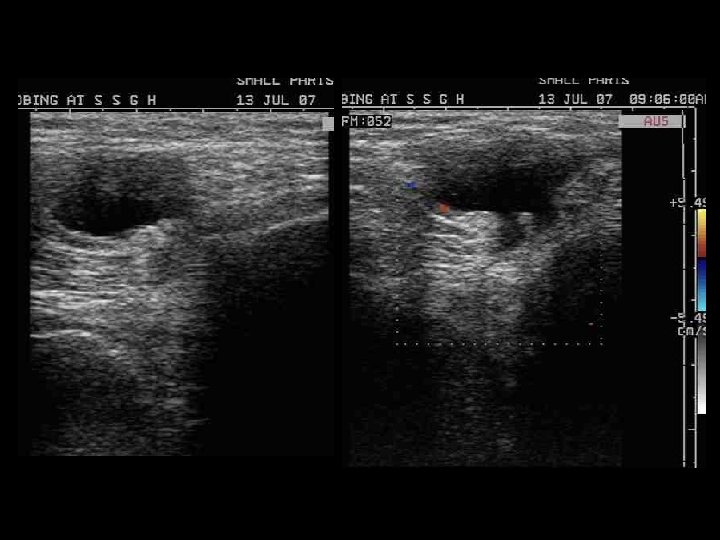

56 yr M, presented with a gradually progressing swelling in posterior region of knee & discomfort.

Backer or Popliteal cyst • It represents fluid distention of a bursa (gastrocnemiosemimembranosus bursa) between the gastrocnemius and semimembranosus tendons via a communication with the knee joint. • Although c/as the gastrocnemiosemimembranosus bursa, it represents a composite of two bursae: – a bursa anterior to the medial gastrocnemius tendon (the subgastrocnemius bursa) and – a bursa between the tendons of the gastrocnemius and semimembranosus tendons

• most common associations include joint effusion, meniscal tear, and degenerative joint disease • MRI gives the typical appearance of the fluid containing structure, with low SI on T 1 W & high SI on T 2 W. • Occasionally the cyst can leak fluid into the calf and cause calf swelling, tightness & pain ( rupture backer cyst ). This may even simulate a calf DVT (deep vein thrombosis). It is easily diagnosed by a careful examination and an ultrasound scan or on MRI.

Baker’s cyst

60 -year-old woman with Baker's cyst. Axial sonogram of posterior knee shows Baker's cyst (arrowheads) with fluid (solid straight arrow) between semimembranosus tendon (curved arrow) and medial gastrocnemius tendon (open arrow). Note subgastrocnemius component (asterisk) of Baker's cyst. Axial proton density-weighted MR image with fat saturation reveals Baker's cyst (arrowheads) with fluid (black arrow) between semimembranosus tendon (curved white arrow) and medial gastrocnemius tendon (open arrow). Note subgastrocnemius component (asterisk) of Baker's cyst. M = medial gastrocnemius muscle.

15 -year-old boy with Baker cyst. Sagittal sonogram of posterior knee shows Baker's cyst (arrowheads). Note septation (solid arrow). Open arrows = medial gastrocnemius tendon, T = tibia. Sagittal proton density-weighted MR image reveals Baker's cyst (arrowheads). Note septation (solid arrow). Open arrows = medial gastrocnemius tendon.